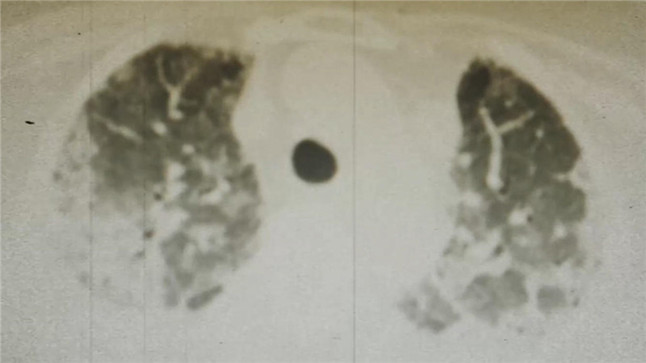

这是一张流感重症患者的胸部CT,这种令人窒息的白肺征象,在医学上是急性呼吸窘迫综合征的典型表现。

这是免疫细胞与病毒厮杀的战场,也是医学影像上触目惊心的白色阴霾。